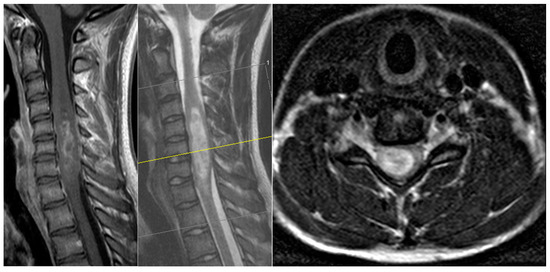

3.4. Case Presentation